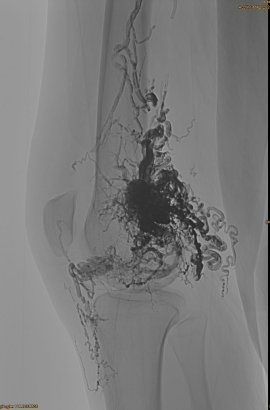

Dastlabki DSA:

Yo'l xaritasi ostida sekin to'ldirish:

Yakuniy natija:

Venozning o'sishi qiyin:

Kechki bosqich, yana bir imtihon zarur, ammo ancha yaxshi: